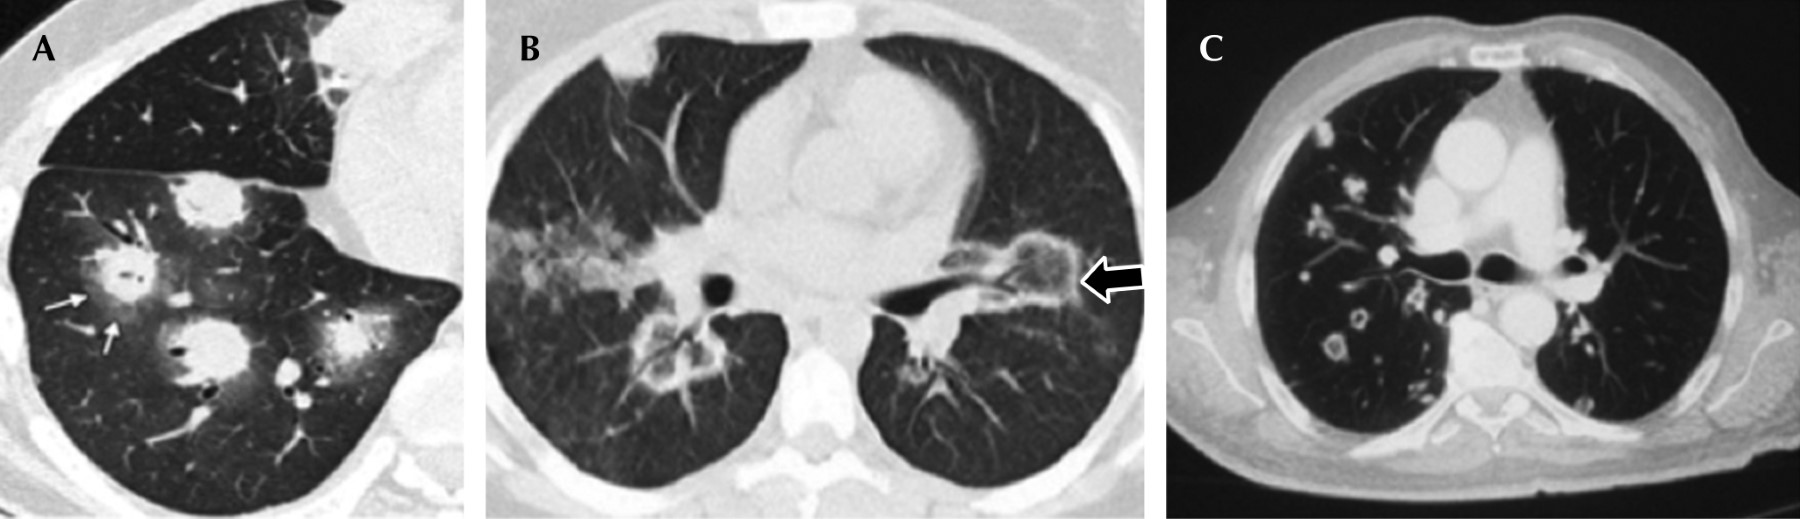

Los hallazgos tomográficos pueden ser variados, predominan la presencia de engrosamiento bronquial, engrosamiento de los septos interlobulillares y sobreafección multinodular.14,15 Existen hallazgos específicos en aspergilosis y mucormicosis, como signo de halo descrito como un nódulo pulmonar rodeado por un patrón en vidrio esmerilado secundario a hemorragia por angioinvasión fúngica (Figura 1A y B). Otro hallazgo consiste en las cavitaciones ocasionadas por la necrosis concéntrica de los nódulos pulmonares, frecuente en las coccidioidomicosis (Figura 1C).